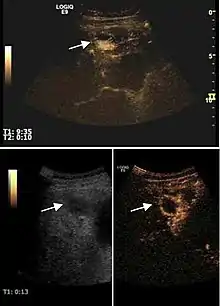

Hepatocellular carcinoma (HCC)

It is the most common liver malignancy. It develops secondary to cirrhosis therefore, ultrasound examination every 6 months combined with alpha fetoprotein (AFP) determination is an effective method for early detection and treatment monitoring for this type of tumor . Clinically, HCC overlaps with advanced liver cirrhosis (long evolution, repeated vascular and parenchymal decompensation, sometimes bleeding due to variceal leakage) in addition to accelerated weight loss in the recent past and lack of appetite.

HCC appearance on 2D ultrasound is that of a solid tumor, with imprecise delineation, with heterogeneous structure, uni- or multilocular (encephaloid form). An "infiltrative" type is also described which is difficult to discriminate from liver nodular reconstruction in cirrhosis. Typically HCC invades liver vessels, primarily the portal veins but also the hepatic veins . Doppler examination detects a high speed arterial flow and low impedance index (correlated with described changes in tumor angiogenesis). The spatial distribution of the vessels is irregular, disordered. CEUS examination shows hyperenhancement of the lesion during the arterial phase. During the portal venous phase there is a specific "wash out" of ultrasound contrast agent (UCA) and the tumor appears hypoechoic during the late phase. Poorly differentiated tumors may have a stronger wash out leading to an isoechoic appearance to the liver parenchyma during portal venous phase. This appearance was found in approx. 30% of cases. The described changes have diagnostic value in liver nodules larger than 2 cm.